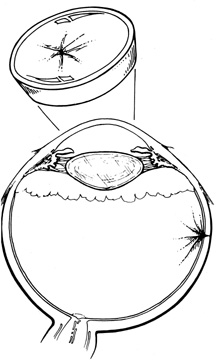

In aphakic patients, limbal entry and drainage often results in vitreous incarceration in the corneal wound. This can be avoided by entering through the pars plana with a 27- or 30-gauge needle on a syringe. The needle is then angled anteriorly through the anterior hyaloid into the anterior chamber, from which aqueous fluid is removed (Fig. 35). If the anterior hyaloid is ruptured and the anterior chamber is filled with vitreous, this technique usually is not effective.

Fig. 35. Anterior chamber paracentesis through pars plana.